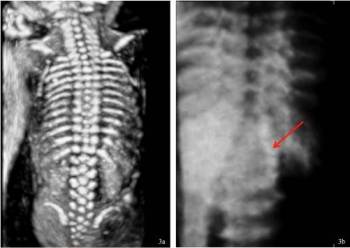

Základní metodou screeningu rozštěpových vad neurální trubice je v těhotenství klasické dvojrozměrné ultrazvukové vyšetření (obrázek č. 2 a 3). Upřesnit diagnostiku může umožnit trojrozměrný ultrazvuk (obrázek č. 3) a magnetická rezonance (obrázek č. 4).

Obrázek č. 3: Trojrozměrné (3D) ultrazvukové vyšetření páteře plodu. Normální nález (3a) při 3D UZ vyšetření ve 21. týdnu těhotenství a abnormální nález (3b) při UZ vyšetření ve 32. týdnu těhotenství. Šipka na obrázku 3b směřuje k místu rozštěpové vady páteře typu spina bifida aperta (rozsáhlá meningomyelokéla).

(Foto: MUDr. Veronika Frisová, Profema)